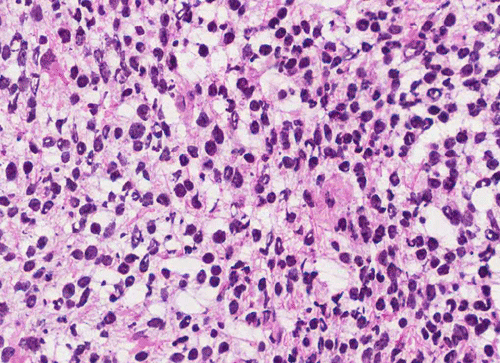

Pathology of the Case: The tumor is composed of neoplastic small blue cells on the cytologic preparation (Pancel C and D) with only minimal amount of cytoplasm. On frozen section (Panel E and F), the tumor cells are packed in solid sheets without specific pattern of arrangement. On permanent sections, the tumor again is composed of solid sheets of small blue cell tumors with rather monotonous nuclei (Panel G and H). In some areas, there is some small neuropil islands (Panel I). No distinct perivascular coronary arrangement is noted.  (Panel J). There is a moderate labeling index on Ki67 (Panel K). The tumor cells are strongly positive for neurofilament proteins (Panel L). Some large stellate, cells positive for glial fibrillary acidic protein (GFAP) are also present and these cells may represent reactive astrocytes (Panel M).

In essence, PPTID is composed of diffuse sheets or large lobules of  uniform cells with mild to moderate nuclear atypia and low to moderate levels of mitotic activity.  Differentiation of grade II and III tumors can be made based upon a combination of mitotic activity levels and neurofilament protein immunoreactivity. Rare mixed tumors exhibiting characteristic elements of both pineocytoma and pineoblastoma have also been classified as PPTID, albeit somewhat controversially. The tumor classification of PPTID originated in 1993 with the work of Schild, et al. reviewing data on 30 patients with pineal parenchymal tumors diagnosed between 1939 and 1991. Of the 30 pineal parenchymal tumors, four were sub-classified as PPTID by Schild and his colleagues 9.

PPTID has a histopathologic picture of a small blue cell tumor. However, the degree of pleomorphism is not as high as pineoblastoma or medulloblastoma. Particularly for the one with better differentiation, the cells would have overall features suggestive of lymphocytes. This would further suggest germinomas as they are associated with a substantial amount of lymphocytes. Search for large germinoma cells would be the diagnostic clue to distinguish these two categories. Histological distinction of PPTID with teratomas, yolk sac tumors, embryonal cell carcinomas, and choriocarcioma components in germ cell tumors is relatively straightly forward. The table below provides comparison of different types of pineal parenchymal tumors.